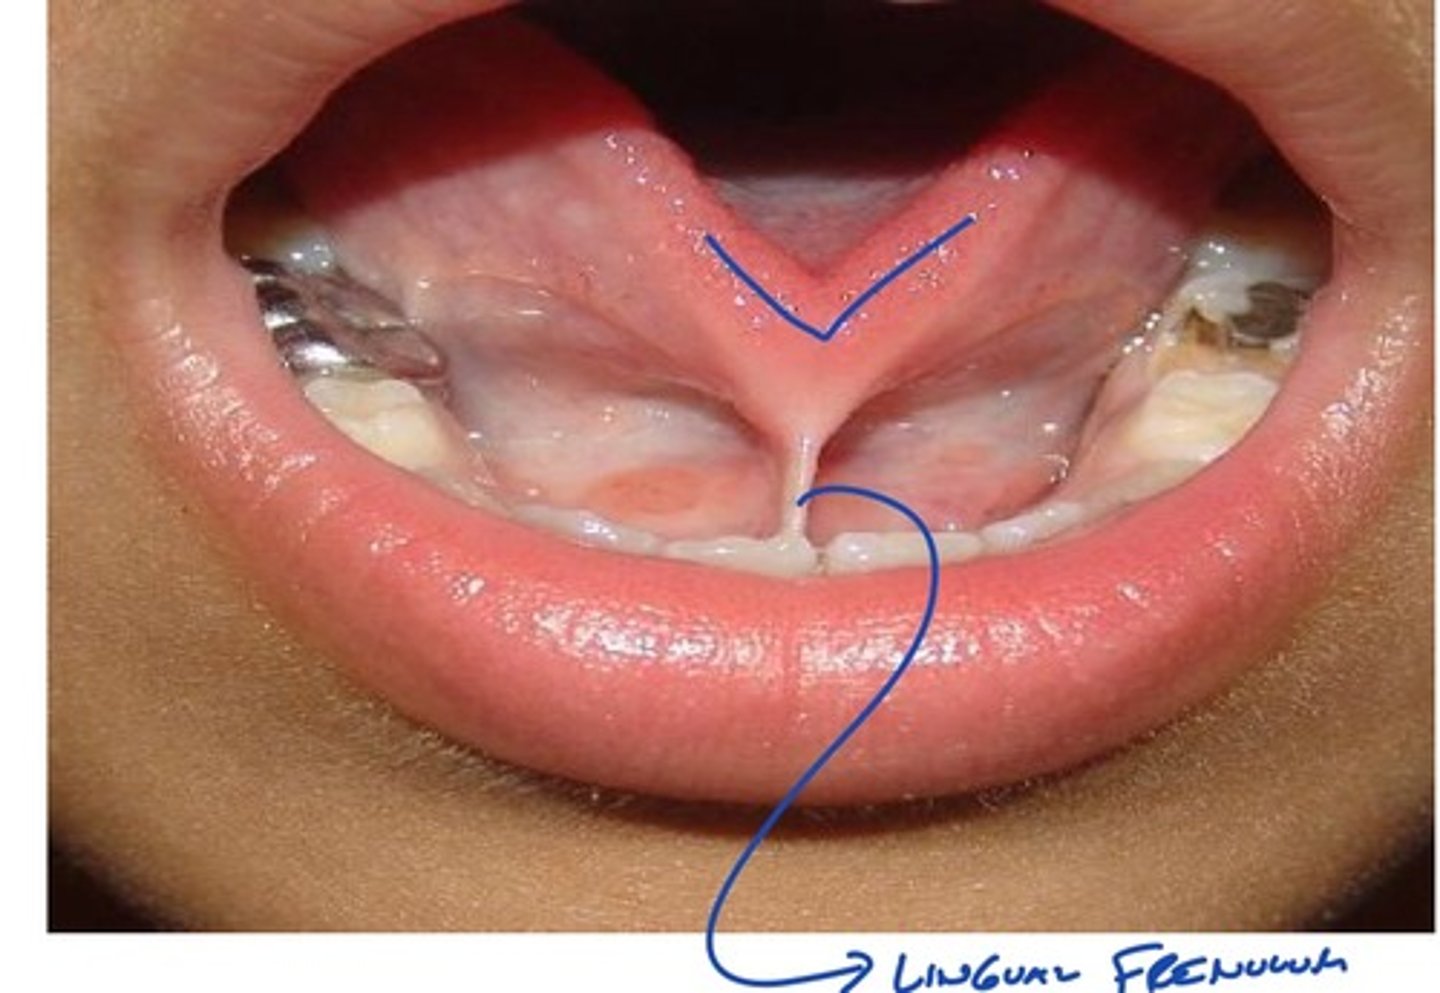

Describe physical variations of the oral cavity: shortened frenulum

-seen in children

-tongue tied: creates speech problems

-can get it clipped